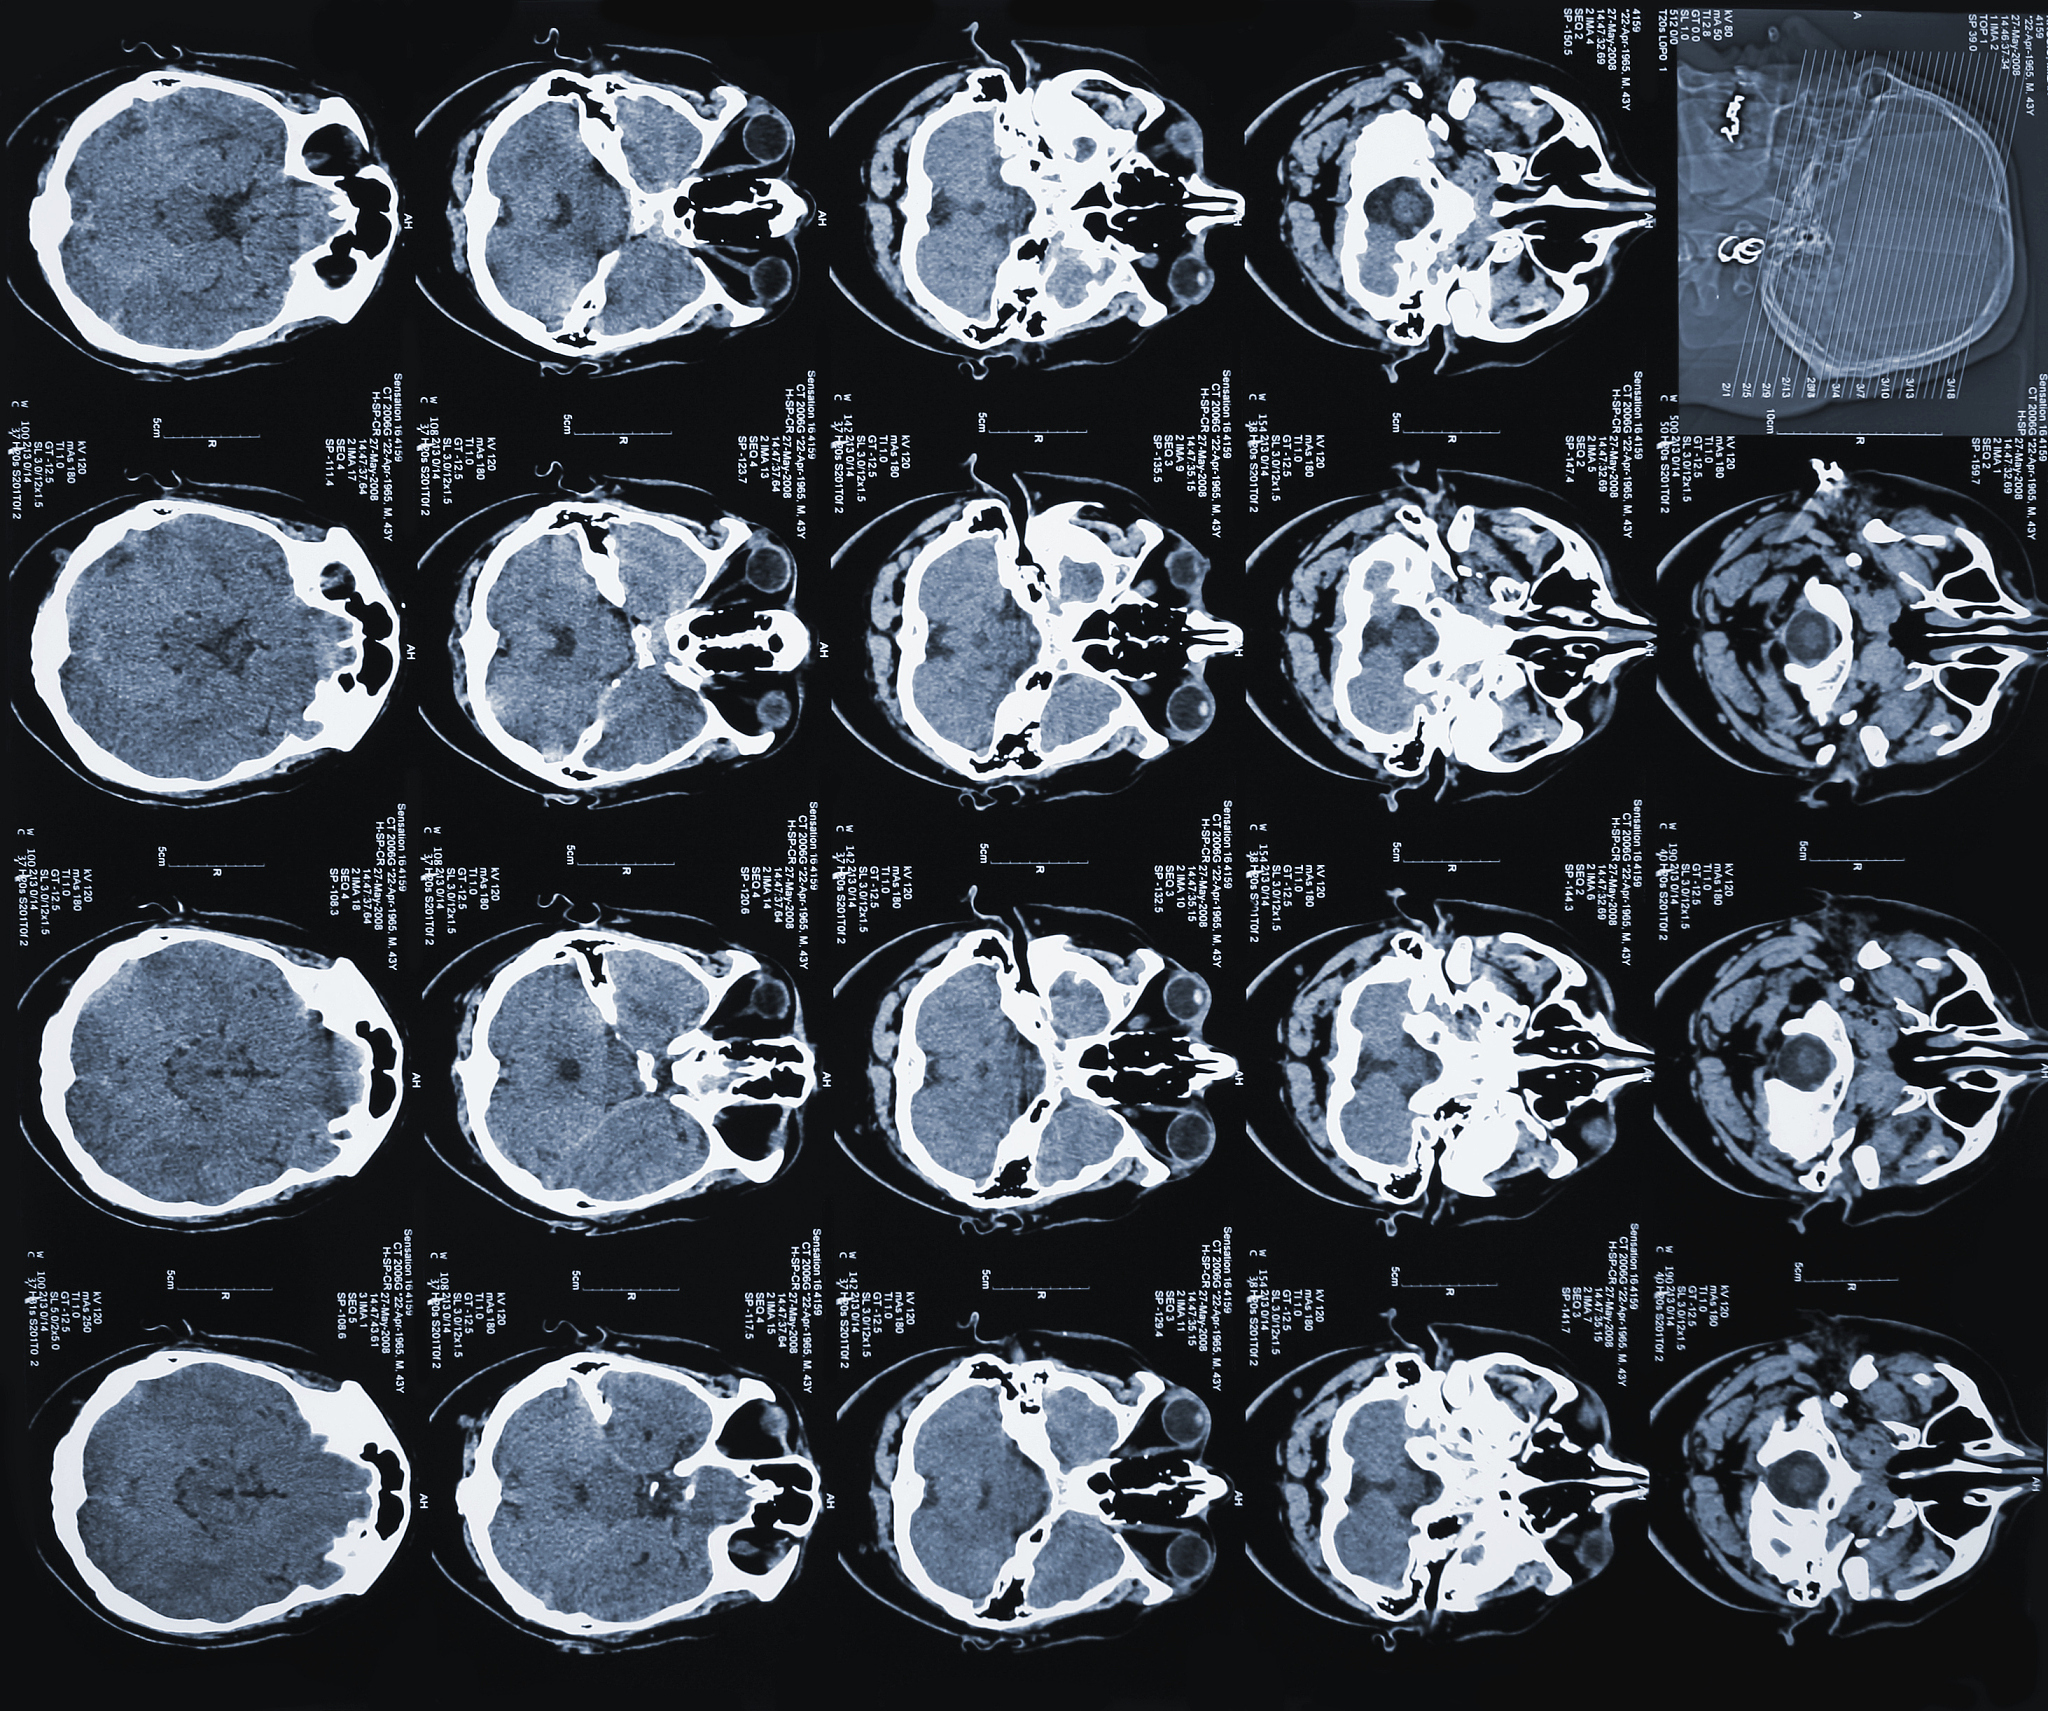

面部CT图数据集是由医学影像数据组成的数据集,包含了人类面部的CT(计算机断层扫描)图像。这些图像通常用于诊断和治疗面部组织和骨骼的疾病,例如面部骨折、颌骨疾病和口腔颌面外科手术等。面部CT图数据集通常包括多个层面的图像,可以用于3D重建和可视化。这些数据集可用于机器学习算法的训练和测试,以自动化面部疾病的诊断和治疗。